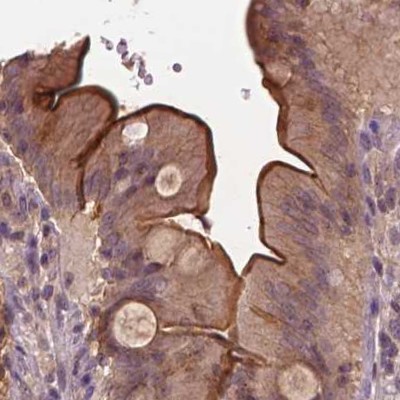

Immunohistochemistry analysis in human duodenum and pancreas tissues using Anti-ANXA13 antibody. Corresponding ANXA13 RNA-seq data are presented for the same tissues.